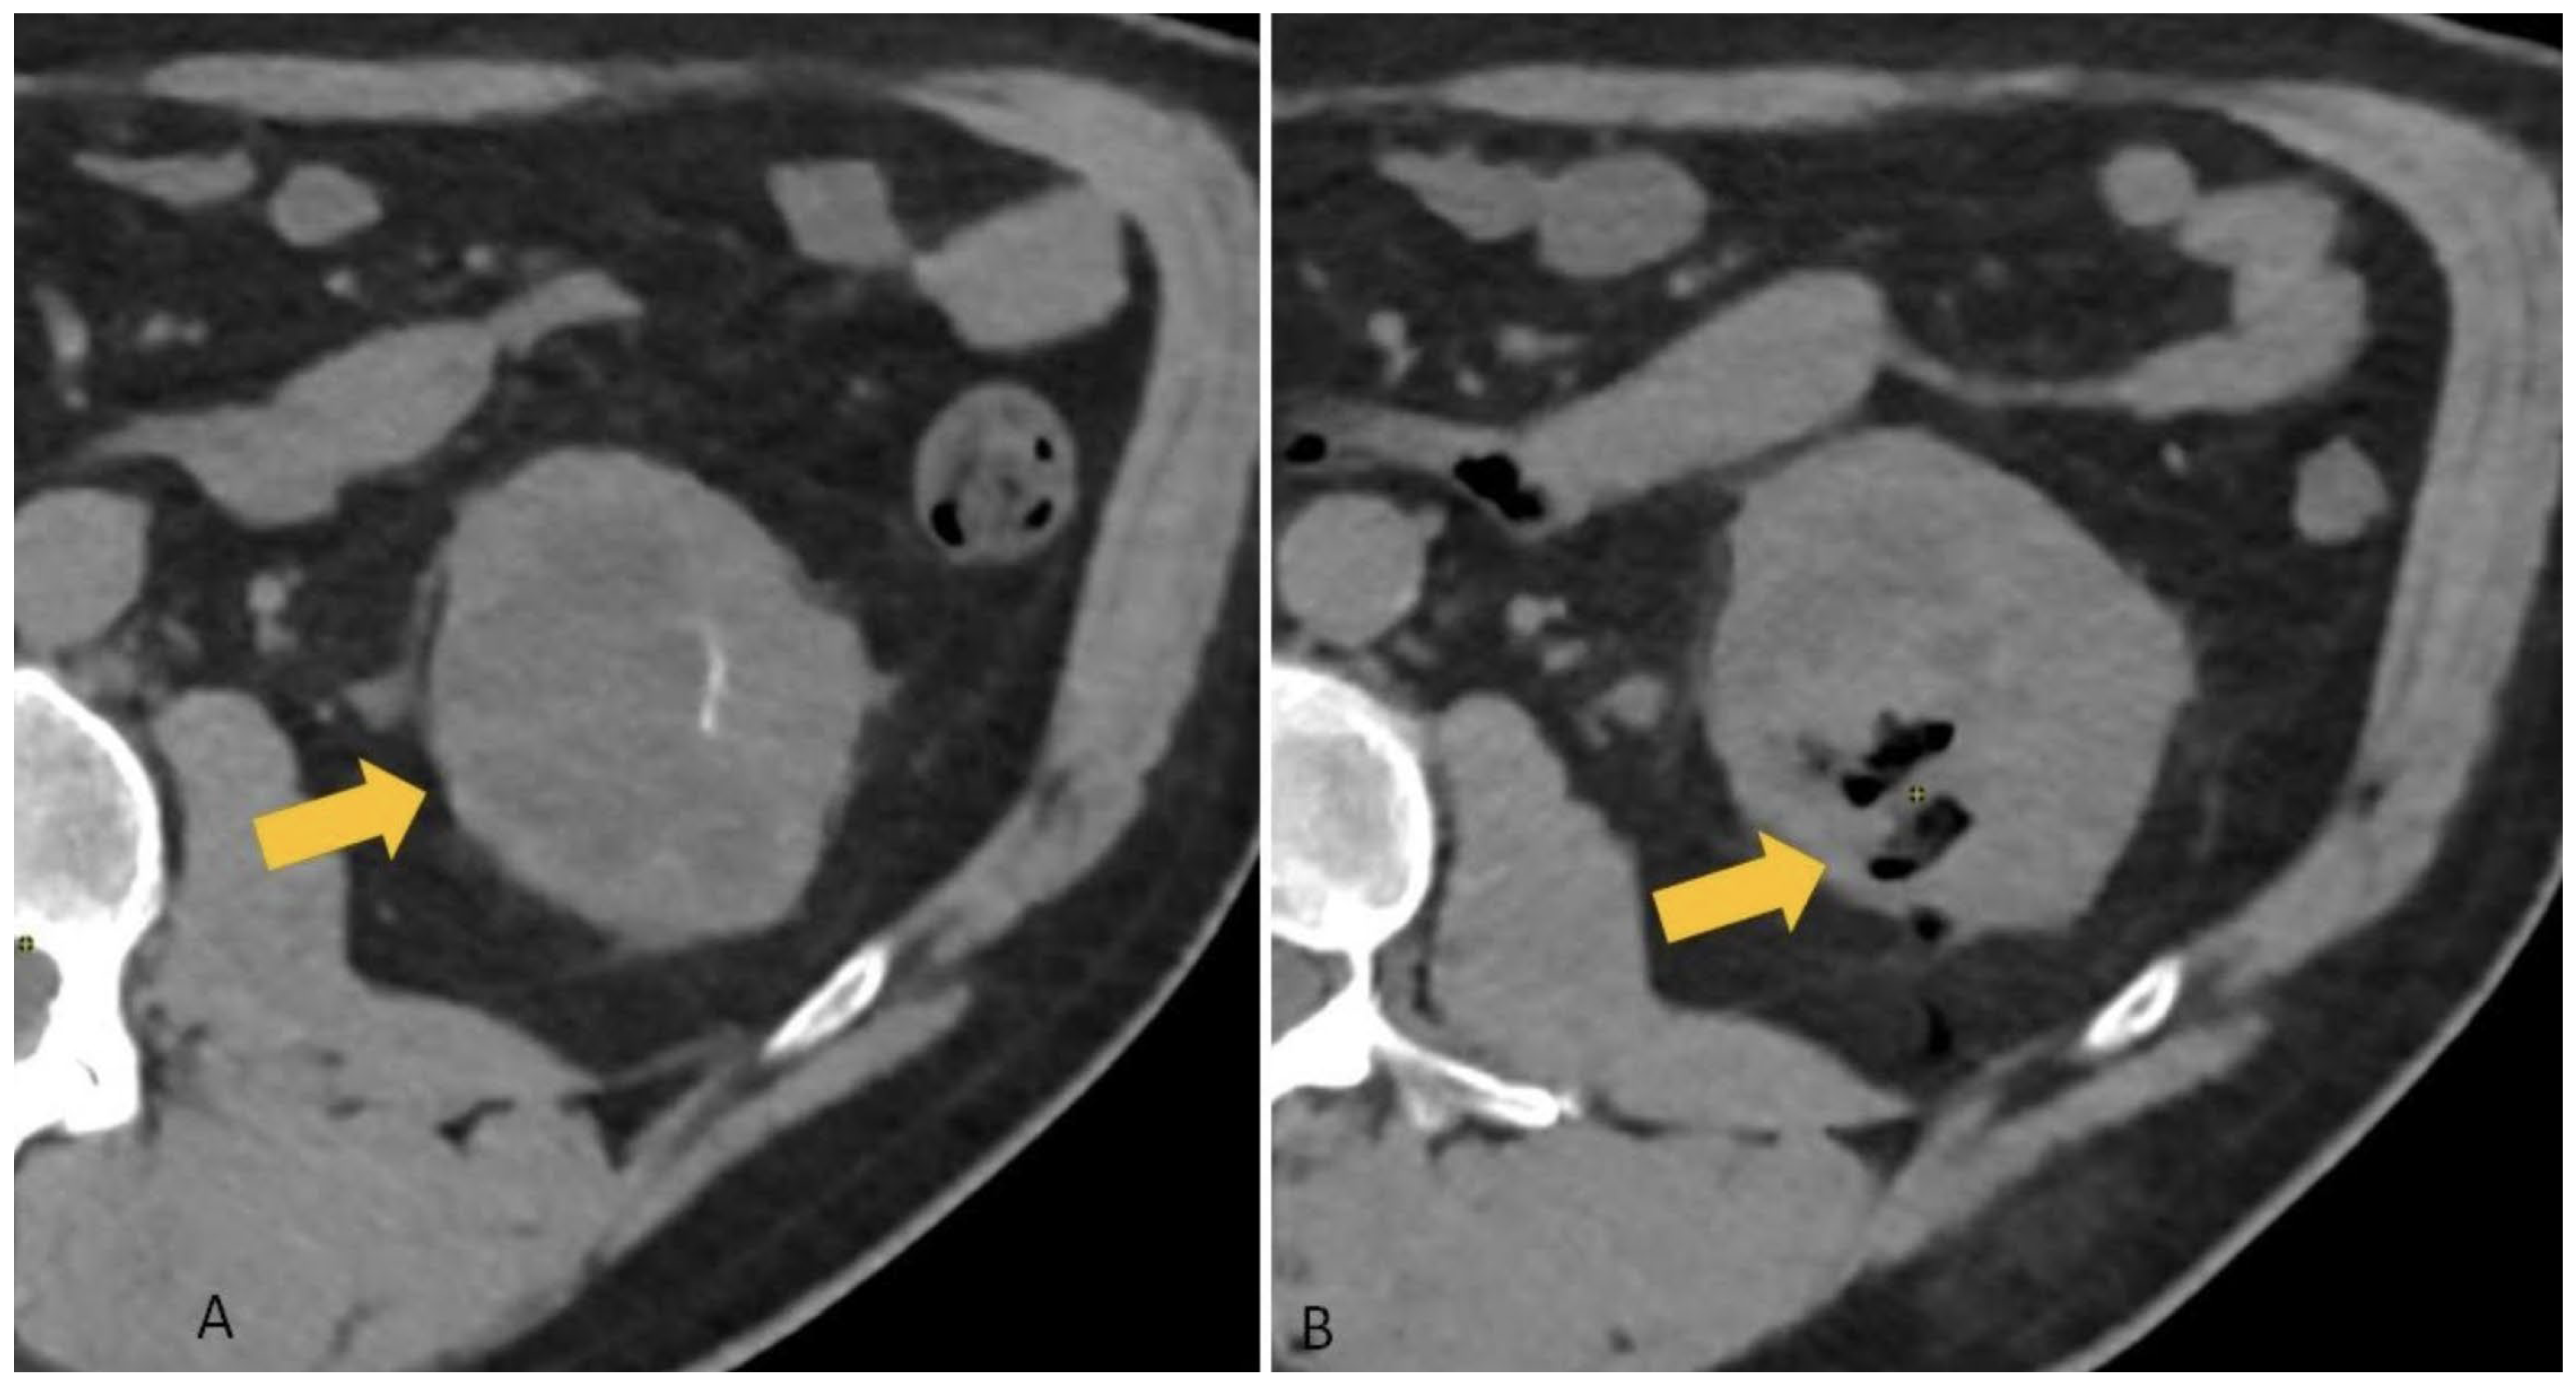

3.2. Incidence of Hemorrhagic Complications

- Group A (Gelfoam):

- Mild hemorrhage: 40% (100/250)

- Mild–moderate hemorrhage: 14.8% (37/250)

- Moderate hemorrhage: 1.3% (3/250)

- Severe hemorrhage: 0%

- Group B (No Gelfoam):

- Mild hemorrhage: 48% (120/250)

- Mild–moderate hemorrhage: 56% (140/250)

- Moderate hemorrhage: 3.6% (9/250)

- Severe hemorrhage: 0.4% (1/250; required embolization)